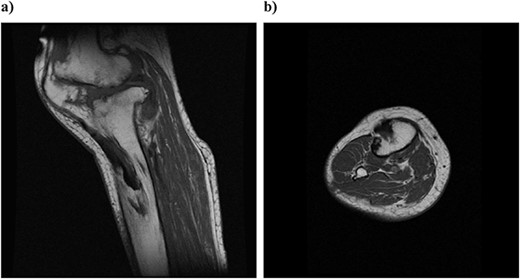

Pathologic specimen from surgery (hematoxylin–eosin staining): (a) 40 times and (b) 100 times. Bone tissue and fibrous tissue are both conspicuous, and ligament-like tissue is partially observed.